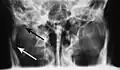

Towne's view of a bilateral condyle fracture. White arrow is a fracture on the neck of the condyle. Black arrow shows the condyle pulled to the medial. The same injury can be seen on the opposite side

Traditionally, plain films of the mandible would be exposed but had lower sensitivity and specificity owing to overlap of structures. Views included AP (for parasymphsis), lateral oblique (body, ramus, angle, coronoid process) and Towne's (condyle) views. Condylar fractures can be especially difficult to identify, depending on the direction of condylar displacement or dislocation so multiple views of it are usually examined with two views at perpendicular angles.[11]